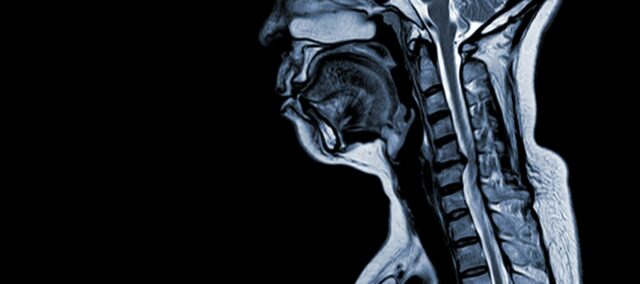

Cervicale spondylotische myelopathie (CSM) is een neurologische aandoening die de belangrijkste oorzaak is van ruggenmergletsel bij volwassenen. Eenvoudig gezegd gaat het om de compressie of beschadiging van het ruggenmerg in de nek, voornamelijk door het natuurlijke verouderingsproces dat de nekwervels aantast. De term 'myelopathie' komt van de Griekse woorden 'myelon', wat 'ruggenmerg' betekent en 'pathos', wat 'ziekte' betekent.